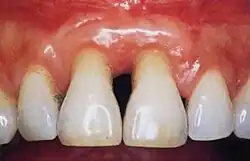

Healthy gingiva can be described as stippled, pale or coral pink in Caucasian people, with various degrees of pigmentation in other races.[15] The gingival margin is located at the cemento-enamel junction without the presence of pathology. The gingival pocket between the tooth and the gingival should be no deeper than 1–3mm to be considered healthy. There is also the absence of bleeding on gentle probing.[11]

Normal gingiva may range in color from light coral pink to heavily pigmented. The soft tissues and connective fibres that cover and protect the underlying cementum, periodontal ligament and alveolar bone are known as the gingivae. The gingivae are categorized into three anatomical groups: the free, attached and the interdental gingiva. Each of the gingival groups are considered biologically different; however, they are all specifically designed to help protect against mechanical and bacterial destruction.[3]

Gingivitis is a common condition that affects the gingiva or mucosal tissues that surround the teeth. The condition is a form of periodontal disease; however, it is the least devastating, in that it does not involve irreversible damage or changes to the periodontium (gingiva, periodontal ligament, cementum or alveolar bone). It is commonly detected by patients when gingival bleeding occurs spontaneously during brushing or eating. It is also characterized by generalized inflammation, swelling, and redness of the mucosal tissues. Gingivitis is typically painless and is most commonly a result of plaque biofilm accumulation, in association with reduced or poor oral hygiene. Other factors may increase a person's risk of gingivitis, including but not limited to systemic conditions such as uncontrolled diabetes mellitus and some medications. The signs and symptoms of gingivitis can be reversed through improved oral hygiene measures and increased plaque disruption. If left untreated, gingivitis has the potential to progress to periodontitis and other related diseases that are more detrimental to periodontal and general health.[10]